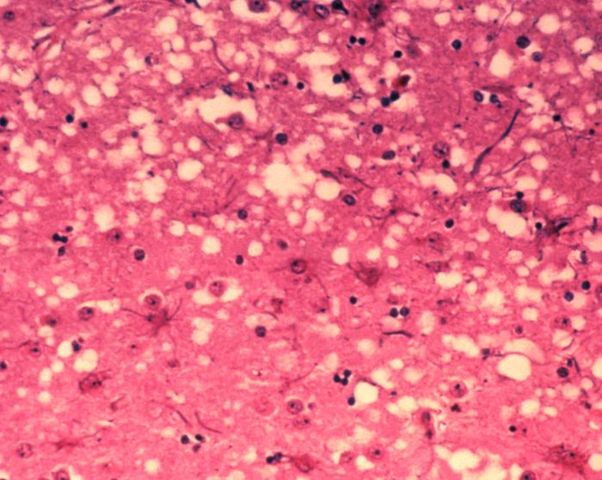

English: This micrograph of brain tissue reveals the cytoarchitectural histopathologic changes found in bovine spongiform encephalopathy. The presence of vacuoles, i.e. microscopic “holes” in the gray matter, gives the brain of BSE-affected cows a sponge-like appearance when tissue sections are examined in the lab.

Nederlands: Deze microscopische opname toont hersenweefsel van een koe die aan BSE gestorven is. Tussen de hersencellen ziet men duidelijk verschillende vacuoles, die deze coupe (weefselsnede) een sponsachtig uitzicht geven.